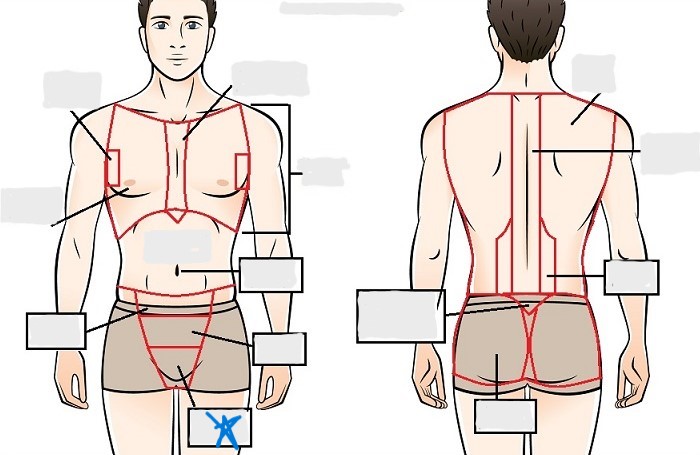

axial

appendicular